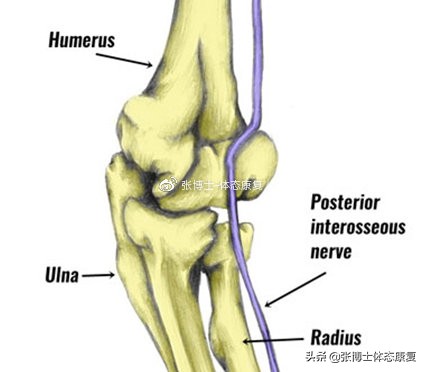

2.桡管综合征

和网球肘的症状类似,肘关节外侧疼痛。但你的手和前臂外侧也可能会感到发麻或刺痛。手腕可能会出现疼痛,疼痛可能还会扩散到上臂。